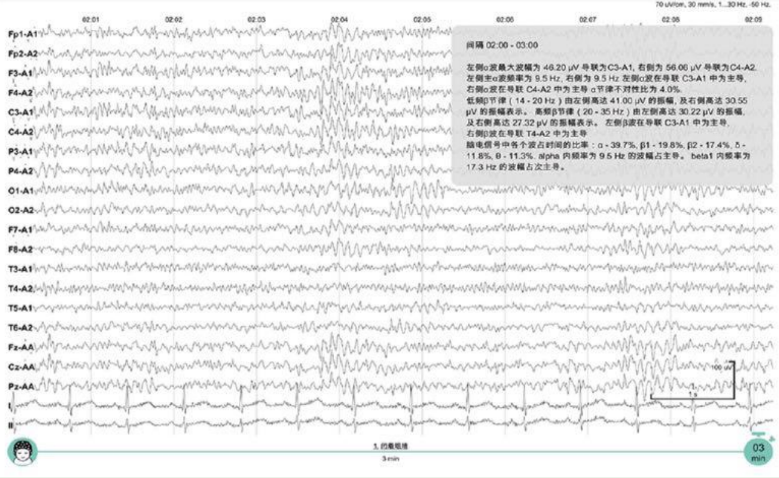

脑电图机用于对患者精神性疾病和脑部实质性病变的分析诊断、脑部功能状态评估。

临床图像